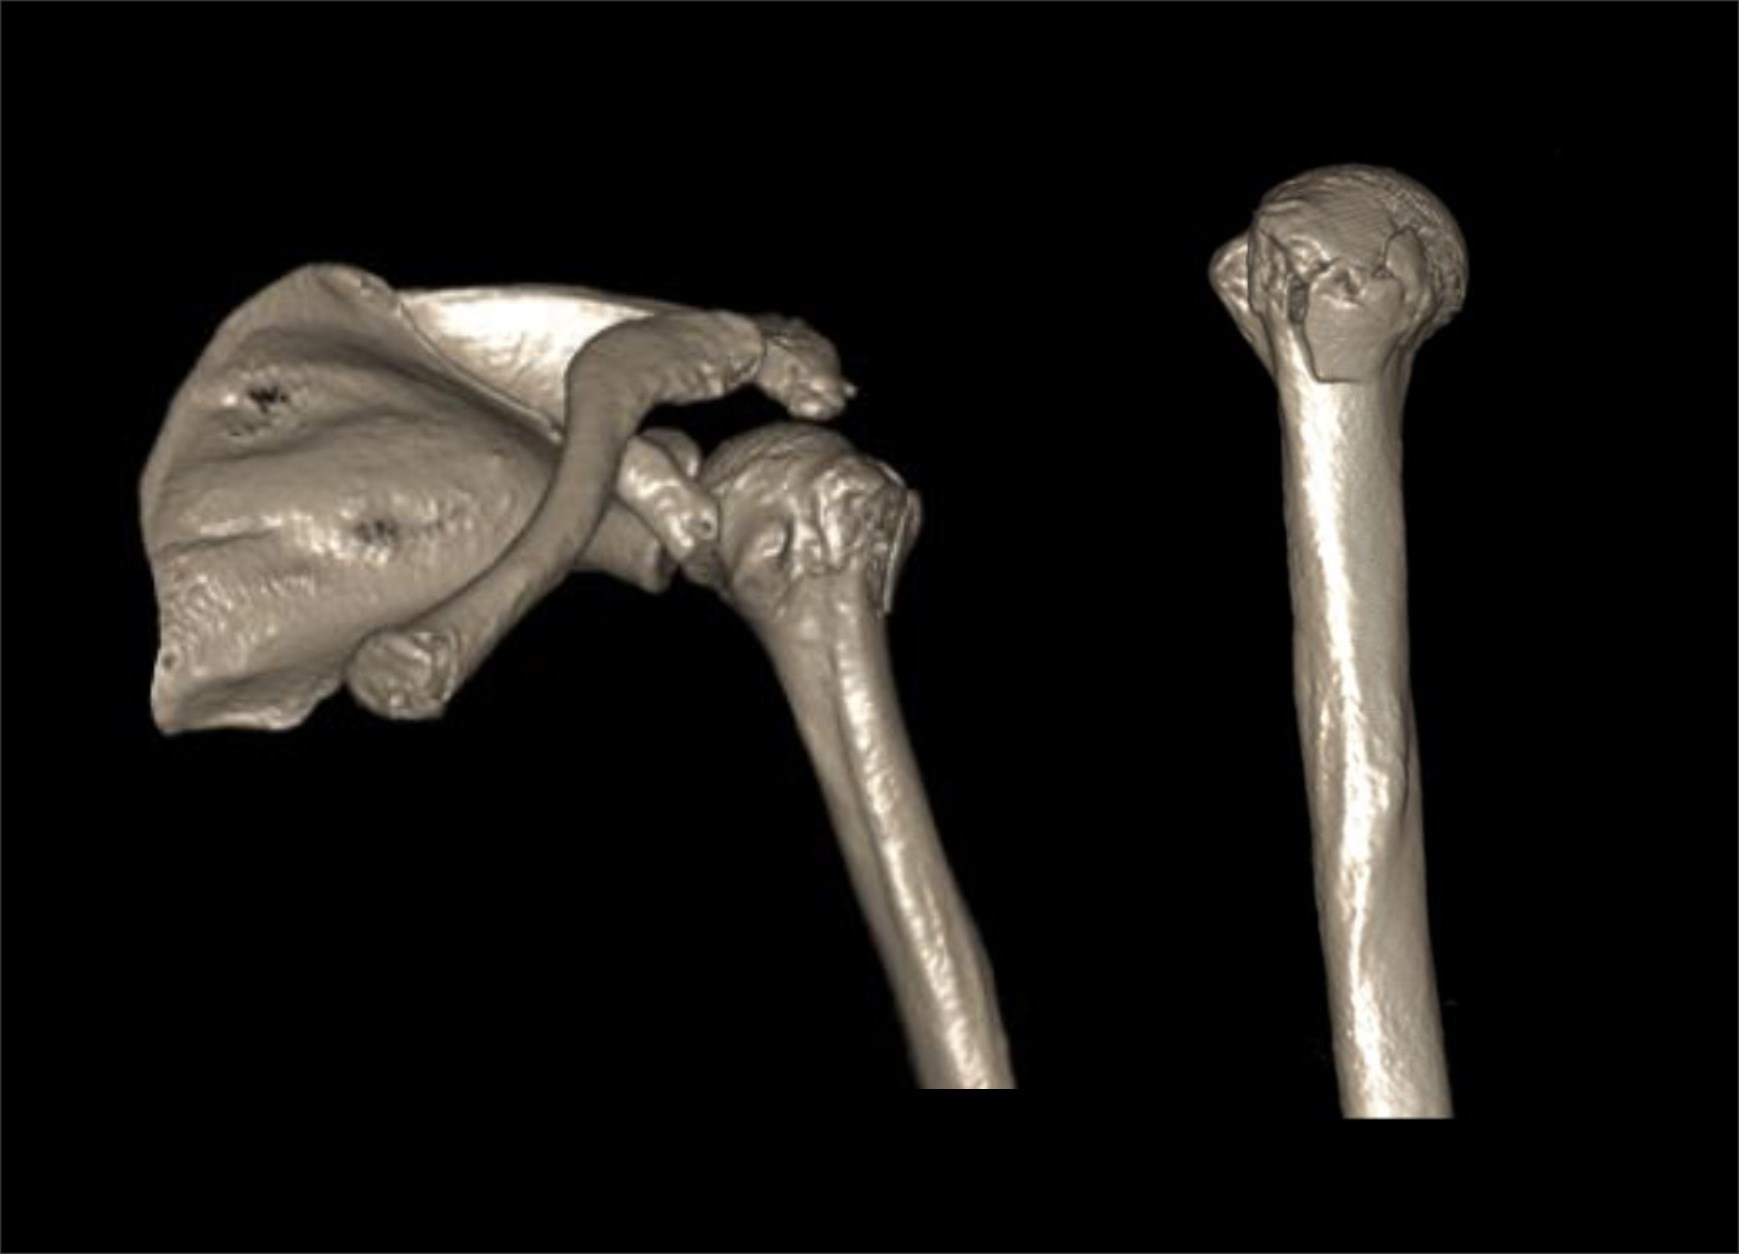

CT shoulder scan is used to evaluate fractures, implant complications and neoplasm. Its ability to view structures in three dimension (3D) is remarkable for surgical planning.

- 3d images to show pathologies clearly.